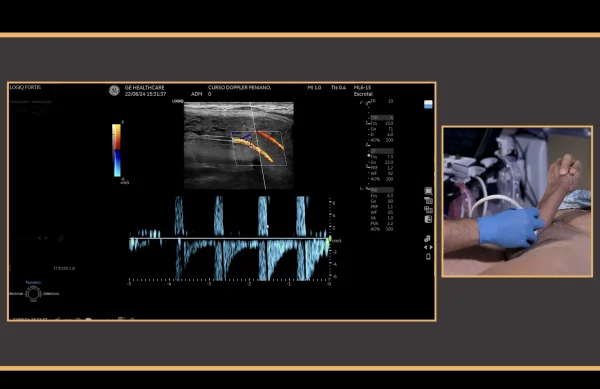

* PDU is the gold standard diagnostic modality in the vascular assessment of erectile function, and it is useful in the therapeutic decision-making process for patients with erectile dysfunction.

This video provides a step-by-step guidance in the conduction of hemodynamics studies using penile Doppler ultrasound (PDU). PDU is the gold standard diagnostic modality in the vascular assessment of erectile function, and it is useful in the therapeutic decision-making process for patients with erectile dysfunction. The video outlines the most important principles for an adequate exam conduction, which includes redosing of vasoactive agents for during erection induction, a rigidity-based assessment of hemodynamic parameters, and an effective detumescence protocol using reversal agents. The conduction of standard PDU examination of a 54 year-old man with erectile dysfunction is described.